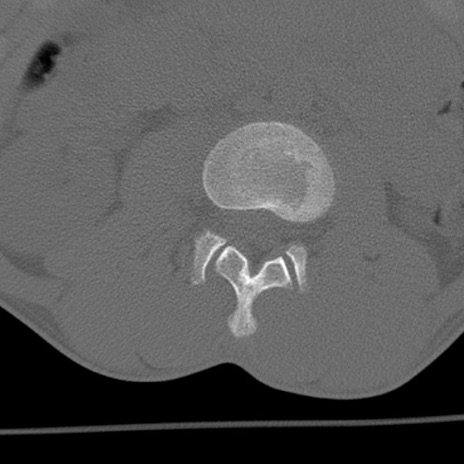

症例3 腰椎CT(横断像)

腰椎CT